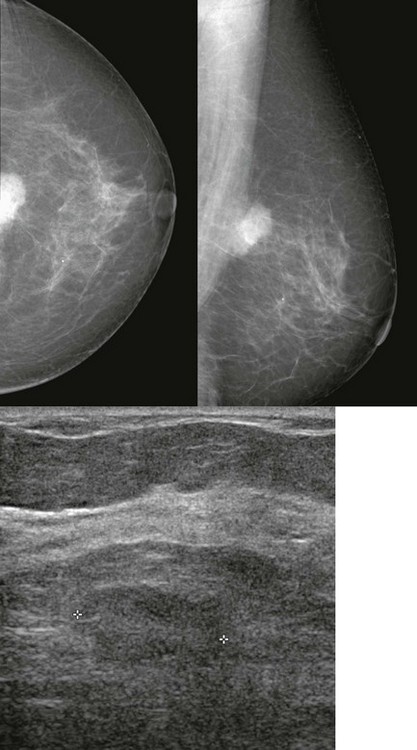

FIGURE 11-2 ILC.

A 49-year-old woman with a firm palpable lump in the right breast. Mammogram is normal in the palpable area that is marked by a triangle. US shows multiple hypoechoic areas with shadowing but no discrete mass, which is characteristic of ILC. (Reprinted with permission from Harvey JA. Unusual breast cancers: Useful clues to expanding the differential diagnosis. Radiology 2007;242:683-694.)

When the tumor is very large, the breast affected with ILC can appear to be getting smaller on mammography—the “shrinking breast” (Fig. 11-3). This is not due to the breast becoming physically smaller, but to the decreased compressibility of the breast tissue that is full of webs of cancer cells. If the contralateral breast compresses to a thickness of 5 cm, a breast with extensive ILC may only compress to 8 cm. Although this results in the appearance of a smaller breast on mammography, breast size is typically symmetric on clinical examination.

FIGURE 11-3 Shrinking Breast.

A 52-year-old woman noted thickening in her left breast. On clinical examination, the breasts are symmetric in size but the texture of the left breast is diffusely thickened. On mammography, the left breast appears to be smaller than the right. Biopsy showed ILC. Did you also notice the one-view asymmetry in the right medial breast? US of this area shows a small hypoechoic mass. Biopsy of the right breast showed IDC.

On US, ILC may present as a defined mass (see Fig. 11-3) but more often presents as ill-defined areas of shadowing without a distinct mass (see Fig. 11-2). The lines and arcs of tumor can produce bands of shadowing, like the edges of a spider web. Although tumor size is often underestimated by US, this modality is more accurate than clinical examination or mammography in assessing extent of disease.

Magnetic resonance imaging (MRI) is helpful in evaluating the extent of disease with ILC, showing more extensive disease than does mammography in 39% of cases. A cautionary note—ILC may show only faint enhancement with progressive kinetics on MRI. The washout pattern is much less common for ILC than IDC. Remember—when interpreting breast MRI and deciding on your management recommendation, the morphologic appearance always trumps the curve.